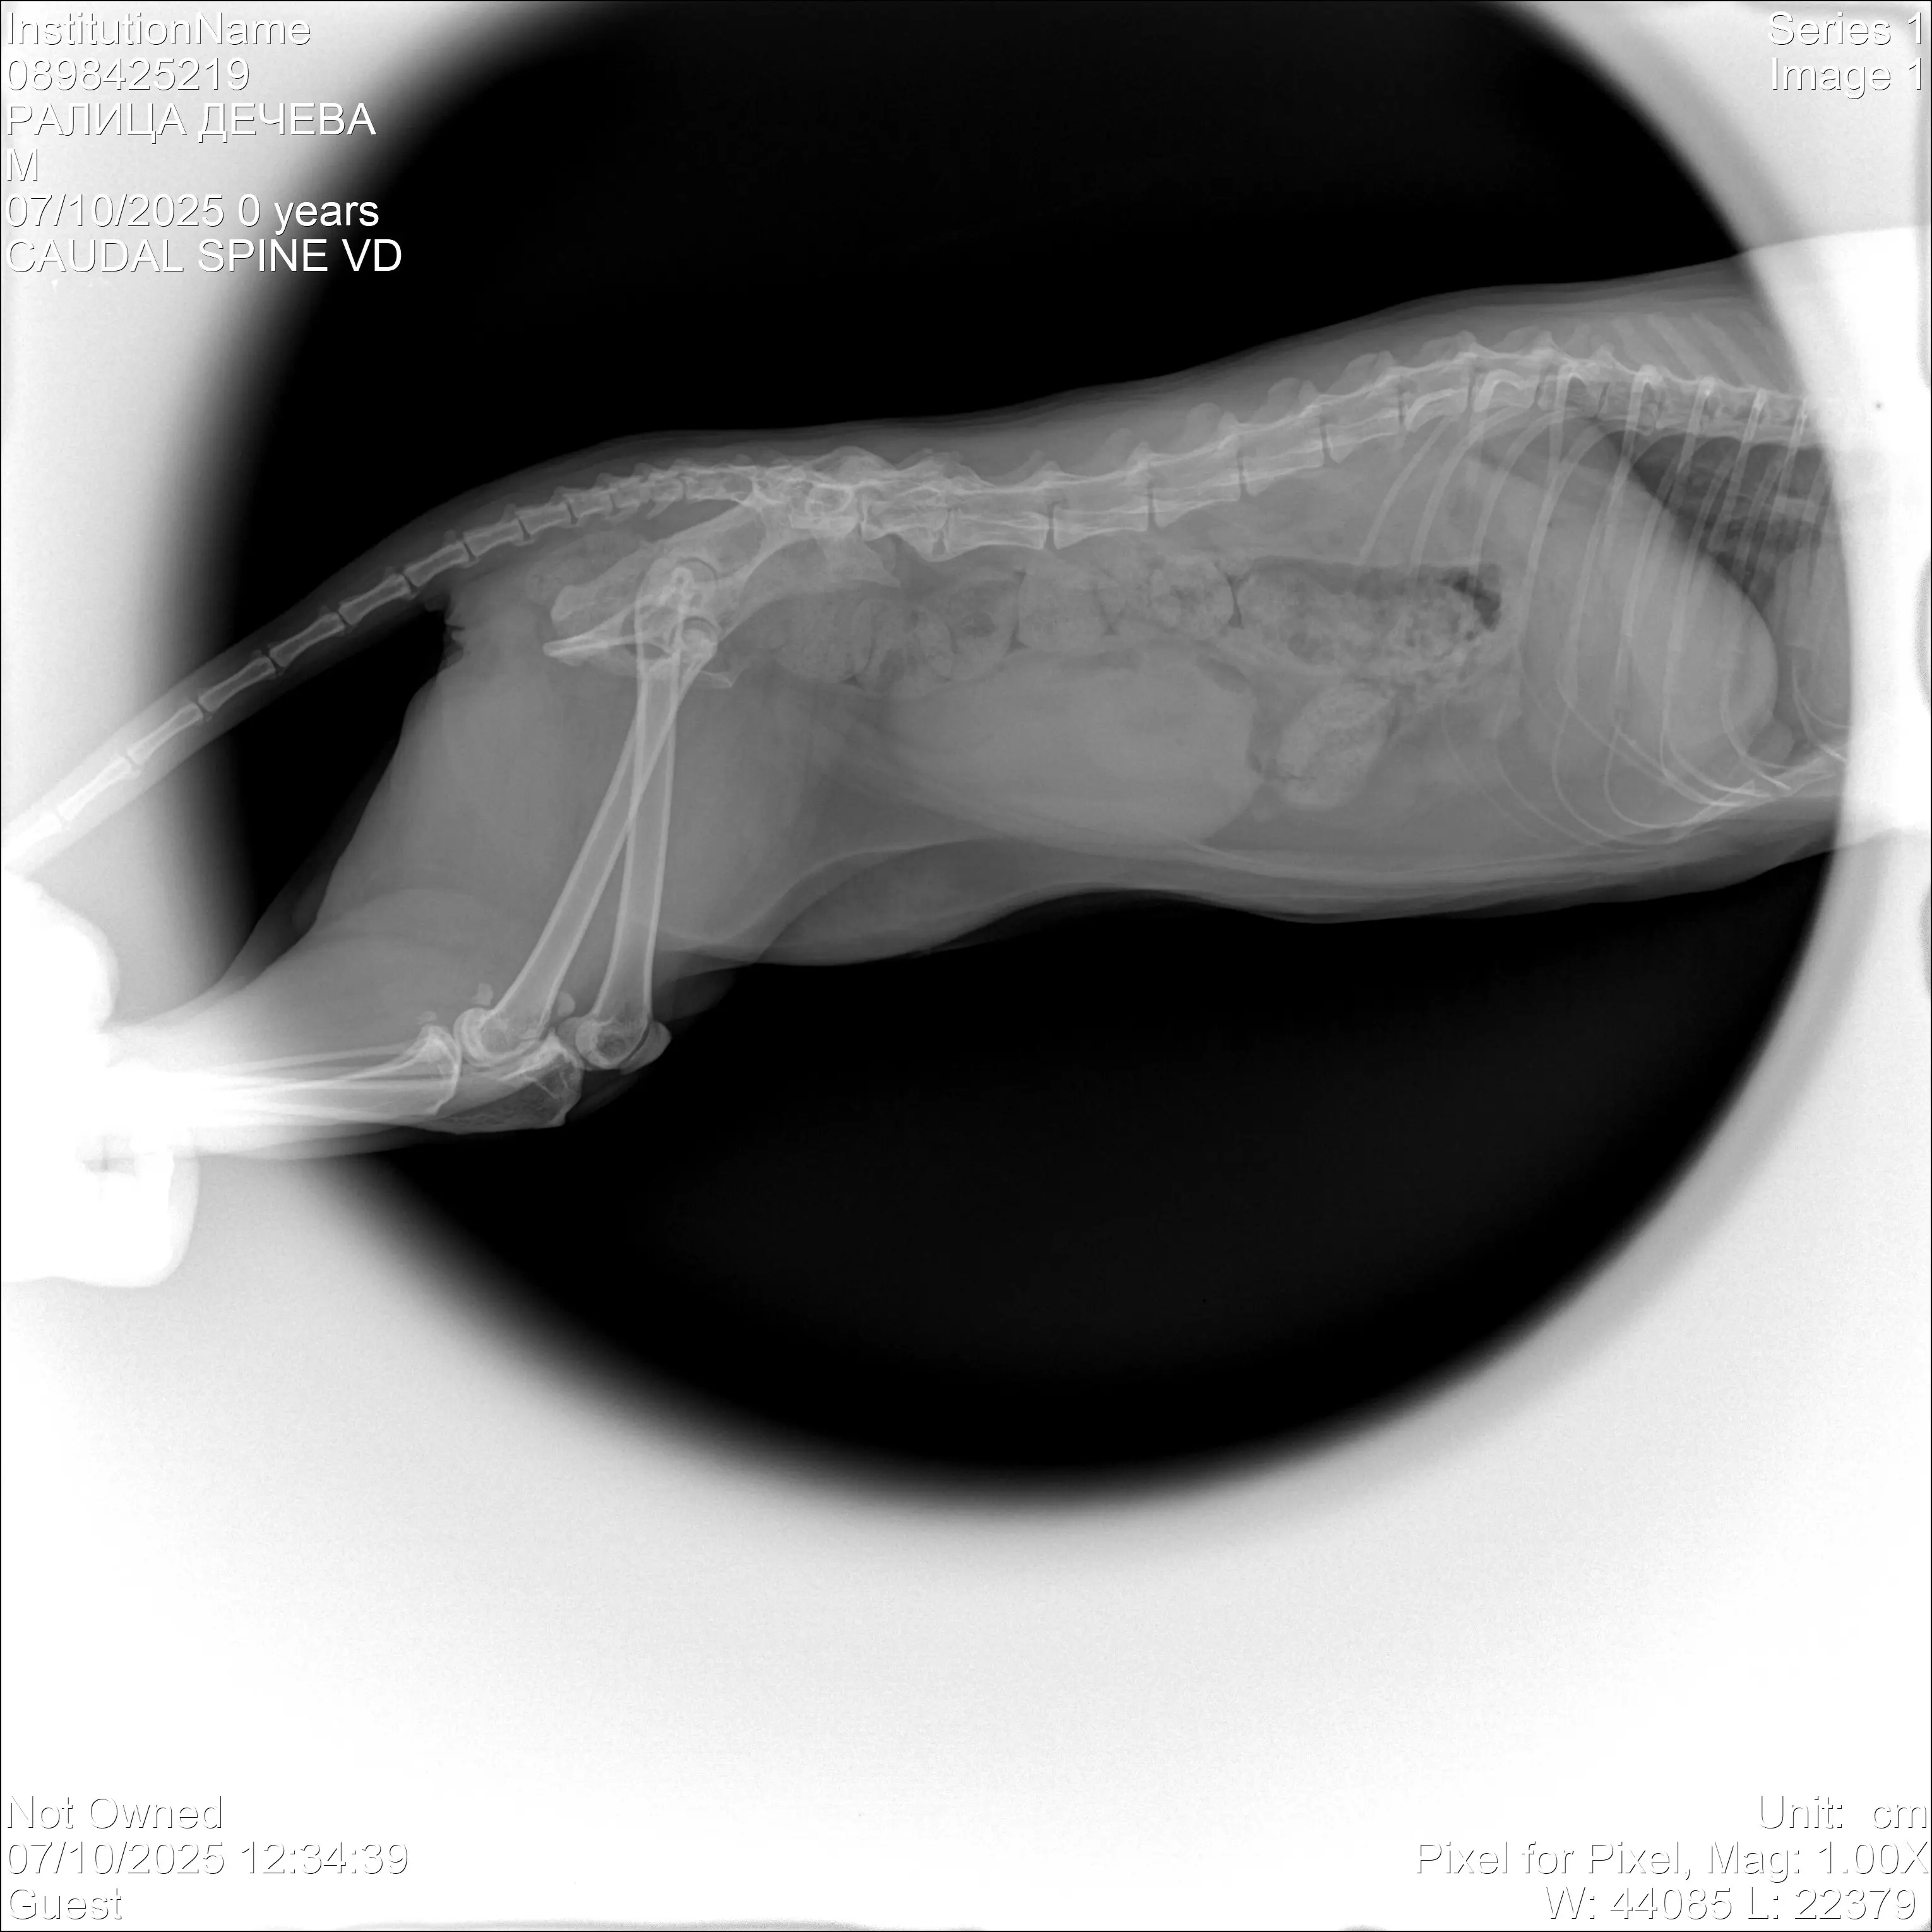

Това е Тигърка. Тя е бездомниче, което започанах да храня преди 2 години. Миналата година изчезна за две седмици и като се върна, разбрах че я е сполетяло нещо лошо, влачеше си и двете крачета. След преглед и консултация с ветеринар, направихме рентгенова снимка и се установи,че е със счупен гръбнак. Прогнозата за Тигърка беше много отчайваща, препоръчаха ми евтаназия, понеже увреждането на гръбначният стълб беше много сериозно и имаше вероятност да не може да се справя сама с физиологичните си нужди. Аз не можах да взема решение за евтаназия веднага и реших да опитаме с лечение - нивалин, милгама и др., както и рехабилитация. Бавно и трудно, но резултат имаше - Тигърка се обслужва сама, единият крайник се възстанови, но другият - няма дълбока чувствителност. Възможността за нея, за да има един по-добър и пълноценен живот е да се ампутира частично крачето и да се направи протеза с титаниева шина.